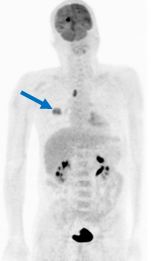

* Vận chuyển tích cực:

Như ta đã biết, iod phóng xạ tập trung vào tuyến giáp theo cơ chế vận chuyển tích cực. Và kể cả ung thư giáp biệt hoá hoàn toàn cũng tập trung iod tương tự. Không phải tất cả các ung thư giáp đều giống như vậy. Hầu hết các khối u giáp không tập trung iod như tuyến giáp bình thường. Người ta đã cố gắng làm tăng độ tập trung iod vào khối u bằng cách dùng thức ăn kiêng có ít iod, hoặc uống vào diuretic (để làm tăng thanh lọc iodine) và tiêm TSH (human recombinal thyroid stinmlating hormone). Một quy trình thông thường khi khối lượng tuyến giáp đã được xác định thì có thể làm chọc dò kim nhỏ. Nếu ung thư thì cắt bỏ toàn phần tuyến giáp. Sau đó cho dùng hormon giáp ngoại sinh và cho uống 185 MBq (5 mCi) 131I để ghi hình toàn thân sau 48 giờ. Mặt khác, một số lớn ung thư giáp thể nang và nhú, còn có ung thư thể tuỷ cũng có thể tập trung iod phóng xạ, cả 201Tl và isonitril – 99mTc cũng có vai trò quan trọng trong phát hiện ung thư giáp vì nó rất ưu điểm là không phải bắt bệnh nhân ngừng điều trị hormon giáp ngoại sinh.